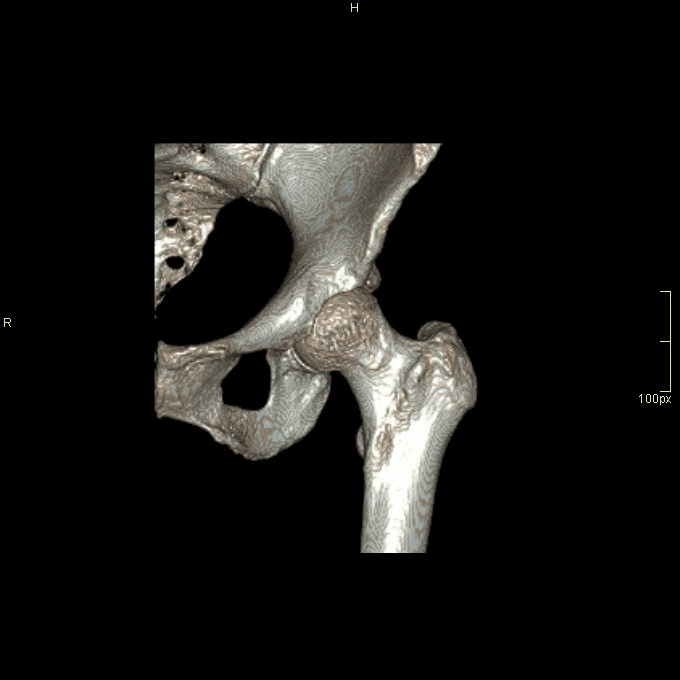

SCAN RANGE: Entire pelvis from iliac crest to below lesser trochanter (Multi-planar reconstructions only of affected hip).

CT Hip Non Contrast- Bone window (axial)

CT Hip Non Contrast- Bone window (coronal)

CT Hip Non Contrast- Bone window (sagittal)

*Extra 3D Reconstructions Available